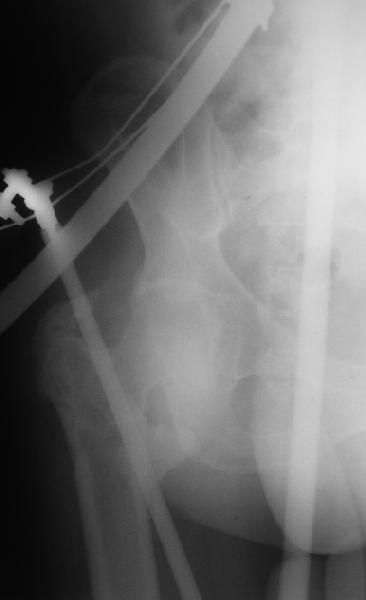

Уважаемые коллеги, помогите определиться с тактикой лечения. Больная, 62 года,жалуется на боли,неопорность левой ноги. Ходит с помощью костылей, укорочение ноги 3 см. Два года назад была оперирована кокой-то накостной пластиной, пластину удалили 4 мес назад. Вопрос такой: предлагать эндопротезирование или делать МОС (что-то по типу стержня Gamma)?За качество снимков извините, по данным МРТ - головка живая

На прошлой неделе оперировали похожего пациента. 2 года после неудачного остеосинтеза PFN в другом регионе. После удаления остатков железа выявилось несращение вертельной области.

Если есть сильное желание фиксировать все-таки гвоздем, советовал бы ввести мощный "джойстик" параллельно оси шейки бедра близко к ее задней стенке, сделать поперечную межвертельную остеотомию и использовать дистрактор таз-бедро.

Поскольку в нашем случае выявилась подвижность, мы наложили дистрактор таз-бедро на 3 дня, и сделали остеосинтез гаммой без остеотомии. То, что произошла "корригирующая остеоклазия" в подвертельной области, выявили после введения гвоздя. Пациент уже уехал домой, будем наблюдать.